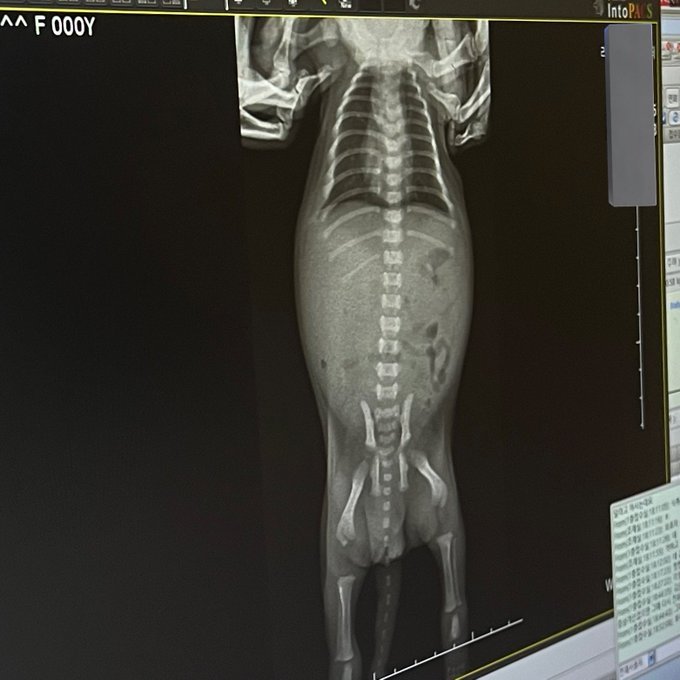

강아지가 분유를 거부해서 병원 갔더니

과식했다함